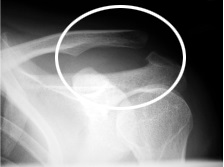

Grade2:肩鎖靱帯の損傷があり、レントゲンで亜脱臼位を呈する。触診で肩鎖関節の圧痛と軽度の動揺性がある。Grade3:肩鎖靱帯損傷に烏口鎖骨靱帯の損傷が加わり、レントゲンで完全脱臼位を呈する(写真2)。触診で肩鎖関節部に一致した突出があり、同部を押すとピアノの鍵盤の様な浮き沈みを認める。

写真2 肩鎖関節脱臼Grade3(○印)